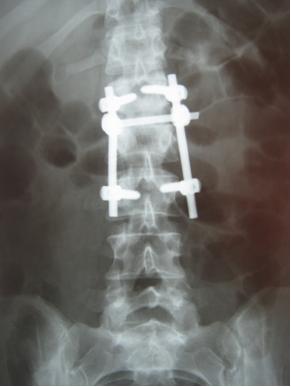

Передняя дискэктомия и корпорэктомия. 1-тело позвонка; 2-кейдж; 3-титановая пластина. нажми на картинку для увеличения

- Передняя дискэктомия (удаление межпозвонкового диска) и корпорэктомия (удаление тела позвонка) с радикальным удалением инфицированных тканей и установкой с целью стабилизации позвоночника аутотрансплантата из гребня крыла подвздошной кости или резецированного (удаленного) ребра или специального титанового кейджа. Обширное удаление передней части позвоночного столба часто создает большие дефекты и негативно влияет на стабильнсть позвоночника. Доказана эффективность применения титановых кейджей для стабилизации позвоночника при воспалительных поражениях. Отсутствуют неблагоприятные последствия, связанные с применением кейджей в присутствии активной гнойной или туберкулезной флоры. Радикальная санация и восстановление стабильности позвоночника являются необходимым условием устранения инфекции и образования костного блока.